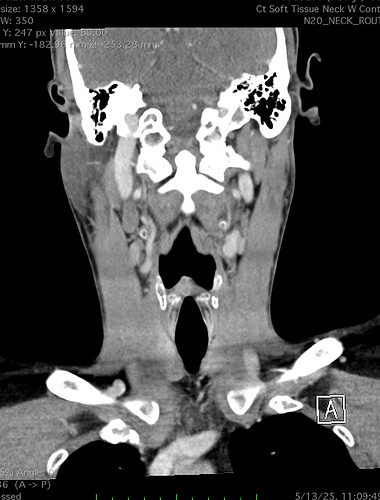

So, 2 years ago was the first time I came across Living with Eagle, filled with descriptions of all my symptoms, and a slew of scans showing very obvious bone chunks in the neck. Since I studied bio in college, and these bones are obvious, I figured I’d take a stab at looking at my own past scans and, low and behold, mild–but present–ossification of my stylohyoid ligament. Perhaps more relevant in my case, in the process of learning enough of the anatomy to understand axial images I noticed another weird thing–my right external carotid artery is in the wrong place. Instead of sitting lateral to my hyoid greater cornu, it’s medial. Hmm.

Tonsil surgery did solve the problem of my tonsils hurting, because they were gone, but no resolution of other symptoms. This was a year ago. I’ve been to PT, SLP, and now back to PT while I trial gabapentin for the neurologist. PT#2 discovered a bunch of significant atrophy in my upper right shoulder/back, and, you guessed it it’s all right sided. I’ve since then, thanks to radiopedia and Netter’s, also explored my images and noticed a few other anomalies in my scans, including an extended right thyroid superior cornu which appears to be pressing strongly into my neck also in the general area of pain, and an occipital artery branching off and wrapping around the internal carotid. Frustratingly these also weren’t mentioned on rads reports. My swallow study by the SLP showed obvious asymmetry with my swallow, but the SLP reported it symmetric and radiology apparently doesnt read the A/P view in their modified barium swallow studies? This is not inspiring faith in the academic institution I attended, but what can I possibly know they dont?